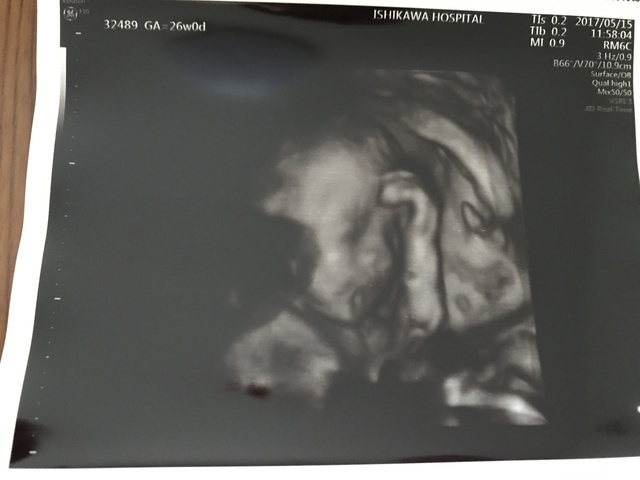

26週0日(26w0d・男の子)|ポコあんミカ さん(40歳)

エコー写真撮影時のエピソード:

初めての自分の子(*´꒳`*)いつも手が顔の近くにあって、このエコーの時はおでこのあたりに手があって、『ちょっと悩んでる?』感じの赤さんです。

少し頭が大きいみたいだけど、問題なくスクスク育ってくれたいます。 もう直ぐ臨月、会えるのをパパママ一緒に待っています。